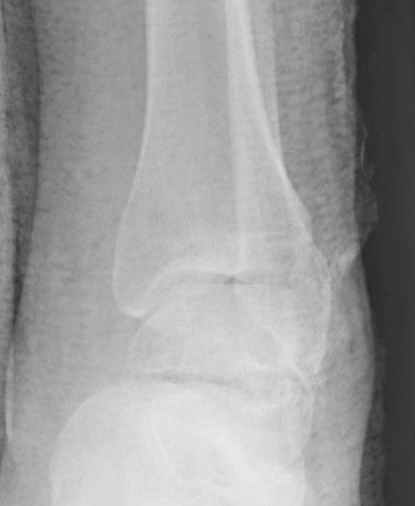

Вдогонку по поводу перелома таранной кости, больная 81, не страдает диабетом, перелом закрытый, в первый же день поступления ограничились временным наружным фиксатором (как на снимке).

Планировалась открытая фиксация после спадения отека, но больная пожелала лечиться по месту жительству в другом штате..

Из-за отека на стопе тактика лечения у всех была

одинаковая: временная наружная фиксация до спадения отека, при изолированных переломах они выписывались домой и через дней 7 госпитализировались на оперативное лечение.

Примеры на снимке...